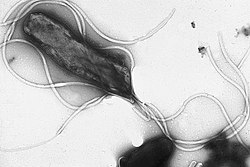

| Electron micrograph of H. pylori possessing multiple flagella (negative staining) | |

Flagellum

The first virulence factor of Helicobacter pylori that enables colonization is its flagellum.[87] H. pylori has from two to seven flagella at the same polar location which gives it a high motility. The flagellar filaments are about 3 μm long, and composed of two copolymerized flagellins, FlaA and FlaB, coded by the genes flaA, and flaB.[30][77] The minor flagellin FlaB is located in the proximal region and the major flagellin FlaA makes up the rest of the flagellum.[88] The flagella are sheathed in a continuation of the bacterial outer membrane, which gives protection against the gastric acidity. The sheath is also the location of the origin of the outer membrane vesicles that give protection to the bacterium from bacteriophages.[88]